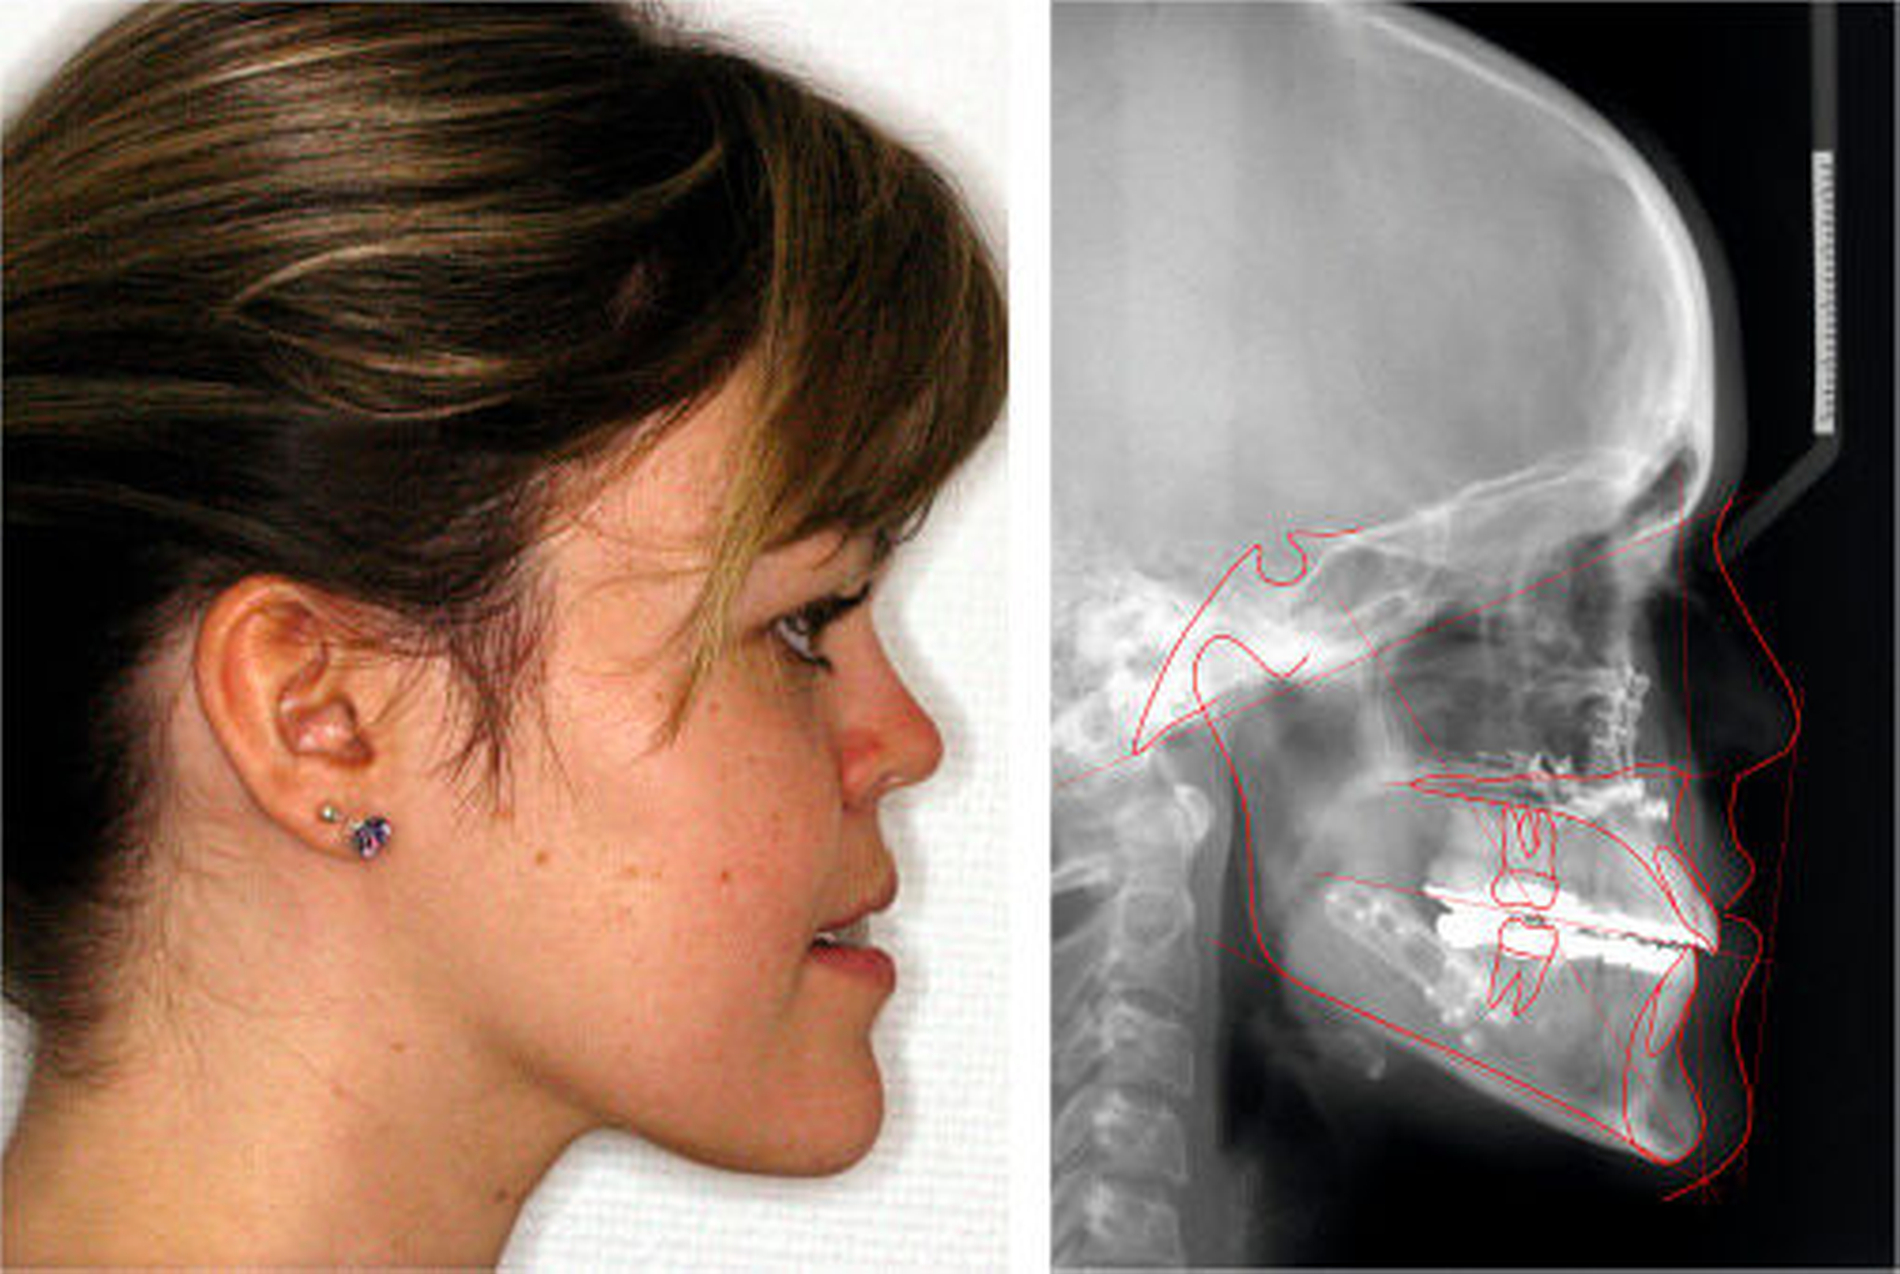

Die Maxilla wurde intraoperativ 3 mm vorverlagert, 3 mm posterior impaktiert und transversal 2 mm erweitert. Die Mandibula wurde mittels sagittaler Spaltung nach Obwegeser/Dal Pont 4 mm rückverlagert. Abbildung 6 zeigt den postoperativen Befund am Fernröntgenseitenbild und von extraoral lateral.